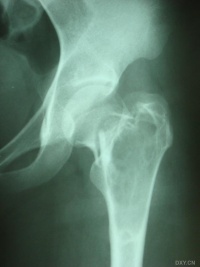

有经验的骨肿瘤医生仅凭X线平片就可以作出骨囊肿的临床诊断。病变灶为边界清晰的液性低密度灶,四壁为薄层的硬化灶壳。病变灶略向近骨骺的干骺部位扩大。病灶非偏心性,也不破坏骨外壳,更不会突破骨质形成骨膜外反应骨,除非是在病理骨折后的愈合期。有时脱落的骨皮质成份落入囊腔中,X片显示被称为“落叶征”(FallenleaforFallenfragment)。当病灶发生在骨盆,CT扫描对病灶部位及囊肿形态的判断有价值。MRI可以明确囊内富含的液性成分。骨ECT扫描表现为外周薄的浓集而中央病灶冷区。

1.好发于4-20岁,多见于5-15岁儿童,少见于成人。好发于股骨颈、股骨上端和肱骨上端。随着年龄增长,囊肿逐渐向骨干方向移动。

3.X线摄片显示长骨干腄端或骨干部位有椭圆形溶骨破坏,边界清楚,其周围可见薄层硬化带,骨皮质可有轻度膨胀变薄。

3.X线摄片显示长骨干骺端有椭圆形密度均匀的透明阴影,病变局限,与

正常骨质间有明显界线,骨皮质膨胀变薄。

X线表现病损为界限清楚的射线透亮区,外有一薄层骨硬化边缘,由于囊肿膨胀性生长,造成骨皮质不规则变薄,X线片常呈假分叶状表现,尤多做囊肿在肱骨或股骨的干骺端向下扩展至骨干,向上扩展虽接近骨骺,但后者可被累及,病理性骨折很常见,囊肿可有骨嵴假象,病理检查见病损为单房的囊腔,其中充满清液,囊内衬以薄层纤维组织,骨折后腔内含血性液体并出现骨痂。

X线平片位于长骨干骺端,呈圆形、卵圆形或柱形,沿长骨纵轴发展,表现为轻度膨胀性生长,局部骨皮质变薄,边缘光整,无骨膜增生。合并病理骨折时,骨碎片向囊内移位,称“碎片陷落征”,有助于鉴别。